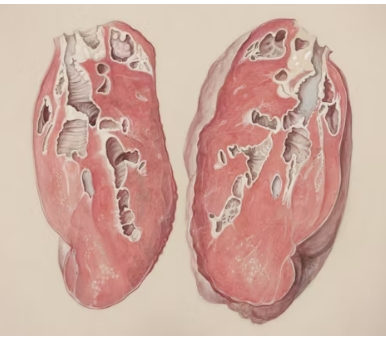

형태학적으로 폐결절은 고형 결절, 부분 고형 결절, 간유리 음영 결절로 구분됩니다.

고형 결절은 CT 상 선명하게 보이는 덩어리 형태이며, 간유리 음영 결절은 뿌옇게 흐린 형태로 관찰됩니다. 두 가지가 혼합된 형태는 부분 고형 결절이라 부릅니다. 이 구분은 추후 진단과 치료 방향을 결정하는 데 중요한 기준이 됩니다.